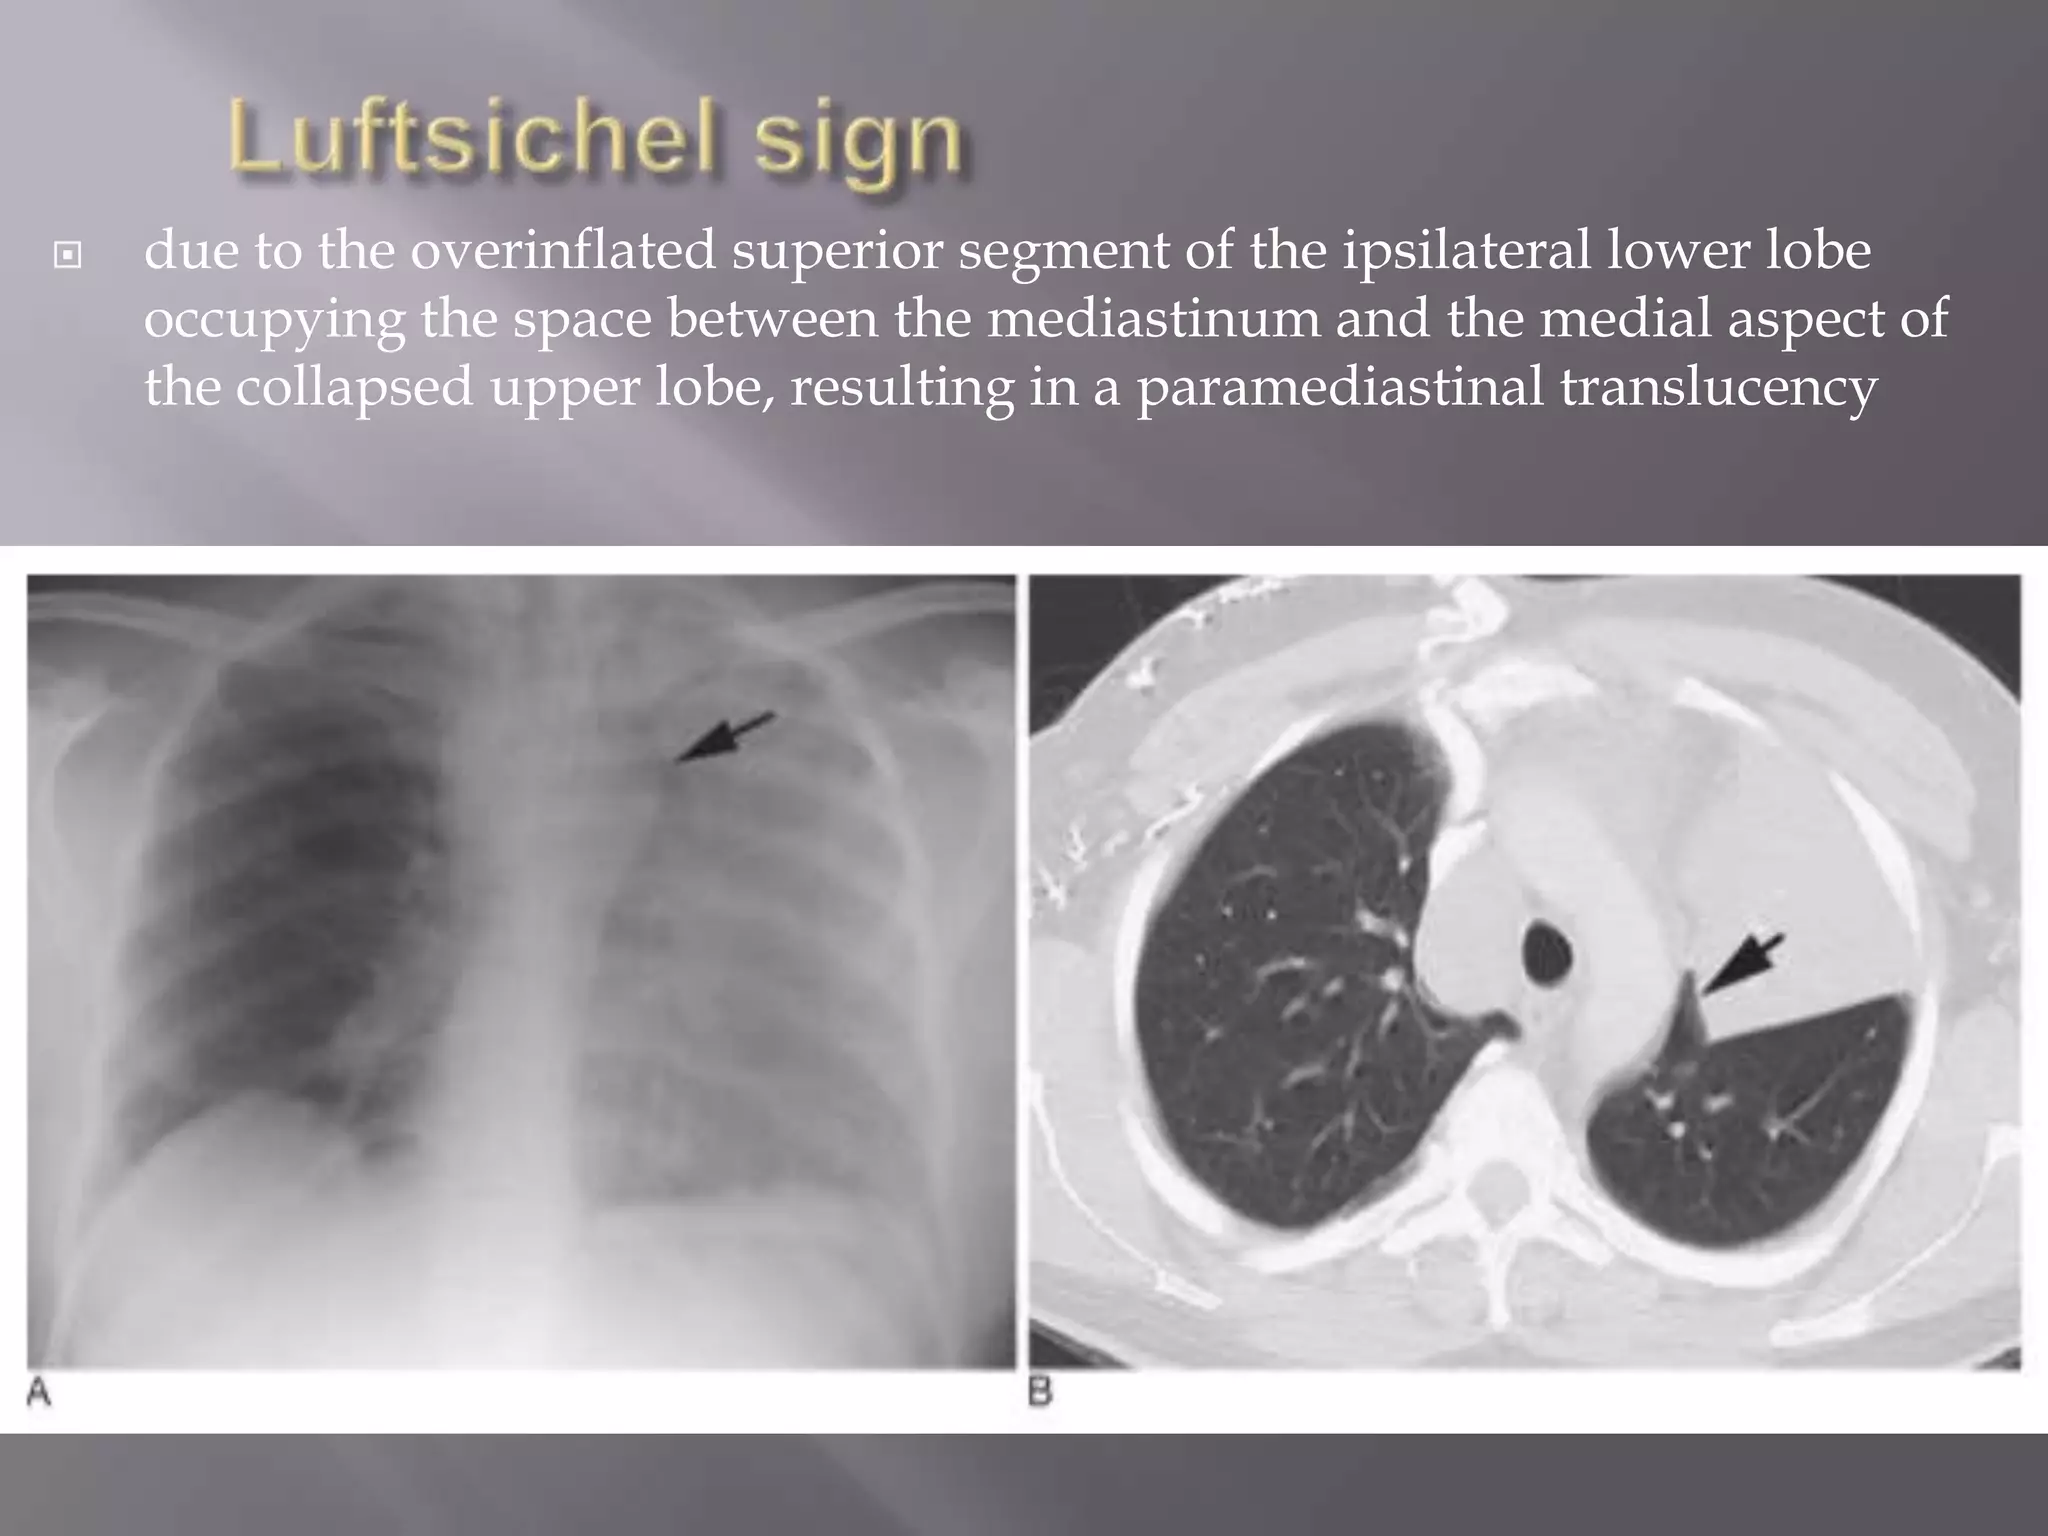

 Luftsichel sign

 due to the overinflated superior segment of the ipsilateral lower lobe

occupying the space between the mediastinum and the medial aspect of

the collapsed upper lobe, resulting in a paramediastinal translucency

 due tothe overinflated superior segment of the ipsilateral lower lobe occupying the space between the mediastinum and the medial aspect of the collapsed upper lobe, resulting in a paramediastinal translucency